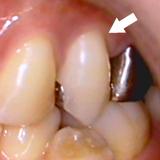

歯槽膿漏・X線写真 | ||

| 歯槽膿漏によって失われた骨(→印の部分)が再生しています。 | ![]() |

【術前】 |

【術後】 |